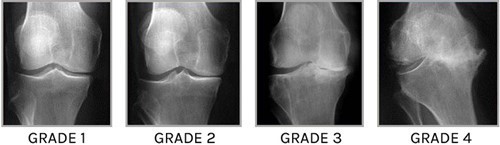

L'Arthrose, c'est à dire la destruction progressive du cartilage d'une articulation, est actuellement un phénomène inexorable.

L’arthrose a par ailleurs une composante osseuse, avec une mauvaise qualité de la jonction os/cartilage (os sous chondral)